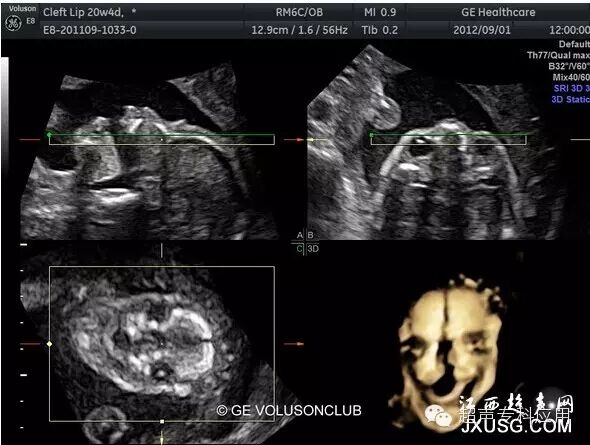

1.1 表面结构的成像 这是三维超声最初在胎儿显像的应用。早孕期可显示整个胎儿的形态以及头颅、腹壁、四肢等;中孕期则能显示胎儿头面部、手指(脚趾)等相对细小的结构。这些表面结构的三维图像,客观逼真,一旦存在胎儿体表的畸形,如唇裂、脑膨出、脊柱裂、脐膨出、腹裂、肢体或手脚畸形,三维成像能够让孕妇及家属一目了然,让产科医生或儿科医生更结合实际情况进行咨询,方便选择下一步的处理方案。虽然三维超声对体表畸形的诊断可能并不比二维超声提供更多信息,这些体表畸形可能在二维声像图上也较容易显示,但孕妇及家属却不理解二维图像,难以想象畸形外观如何、有多严重。为了更人性化的服务,目前,也有不少医院或产院对孕妇提供“胎儿照相”;四维超声观看胎儿运动并录像,以留作纪念。三维表面成像的重要条件是感兴趣区域前方一定要有足够的羊水,而且不能被肢体、脐带等遮挡。羊水过少或晚孕期胎儿充满官腔时,三维表面成像则有较大困难。

胎儿唇裂表面三维成像

1.6 胎儿上腭的三维超声成像 对于唇裂胎儿,产前往往需要评估上腭的情况,以咨询双亲。有文献报道了利用三维重建面部反观冠状平面检查胎儿上腭,发现诊断唇裂的敏感性为95%,假阳性率7.7%;上牙槽裂的敏感性为84.5%,假阳性率7.2%;硬腭裂的敏感性89.7%,假阳性率15.6%。

胎儿唇腭裂三维成像-右下角三维冠状面显示腭裂

胎儿唇腭裂三维容积对比成像重建显示上腭